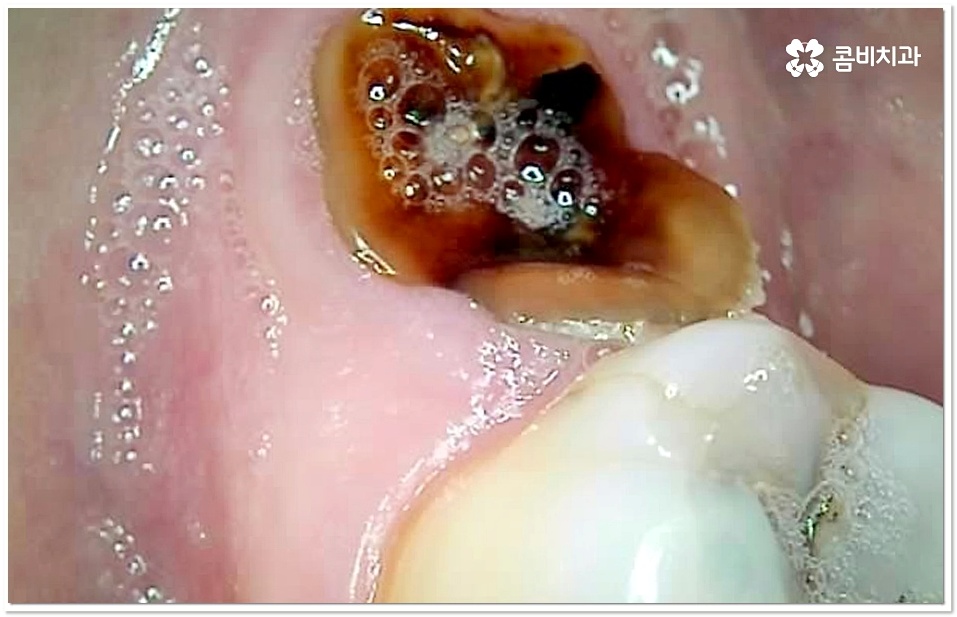

출처 아카이브 열기충치는 많은 분들이 살면서 한번쯤 앓는 대표적인 구강 질환 중 하나로, 원래 명칭은 치아우식증이지만 까맣게 변하는 모습이 마치 벌레먹은 것과 같다고 해서 충치라고 불리고 있습니다. 충치는 충치균이 구강 내 잔여 음식물 속 당분을 먹고 증식하면서 분출하는 산으로 인해 치아 겉면부터 부식이 이루어지고 점점 안쪽으로 손상이 진행되면서 생기는 거예요.

치아는 한번 손상이 일어나면 자연 회복되지 않으며 구조상 안쪽 조직이 더 무르기 때문에 충치균이 깊이 침투할수록 병증이 더 빨리 악화되는 경향을 보이고 있는데요. 그러므로 충치가 생겼을 때 초기에 치과로 내원하셔서 어금니 충치치료 와 같이 제대로 된 대처를 하는 것이 굉장히 중요하다고 할 수 있습니다.

충치 초기에는 손상이 크지 않고 대부분 겉면인 법랑질에 국한되는 경우가 많아 해당 부위를 깨끗하게 삭제한 후 레진으로 직접 때우는 방법을 통해 보다 빠르고 간편한 수복을 할 수 있어요. 그러나 충치가 더 진행되면 손상 부위가 넓고 깊어지기 때문에 레진 처치는 적합하지 않으므로 인레이나 온레이와 같이 보철물을 만들어 끼워주는 방법을 이용하고 있는데요. 특히 어금니는 씹는 힘을 많이 받는 치아이기 때문에 보통 인레이와 같이 내구성이 더 높은 어금니 충치치료 방법을 많이 쓰고 있어요.